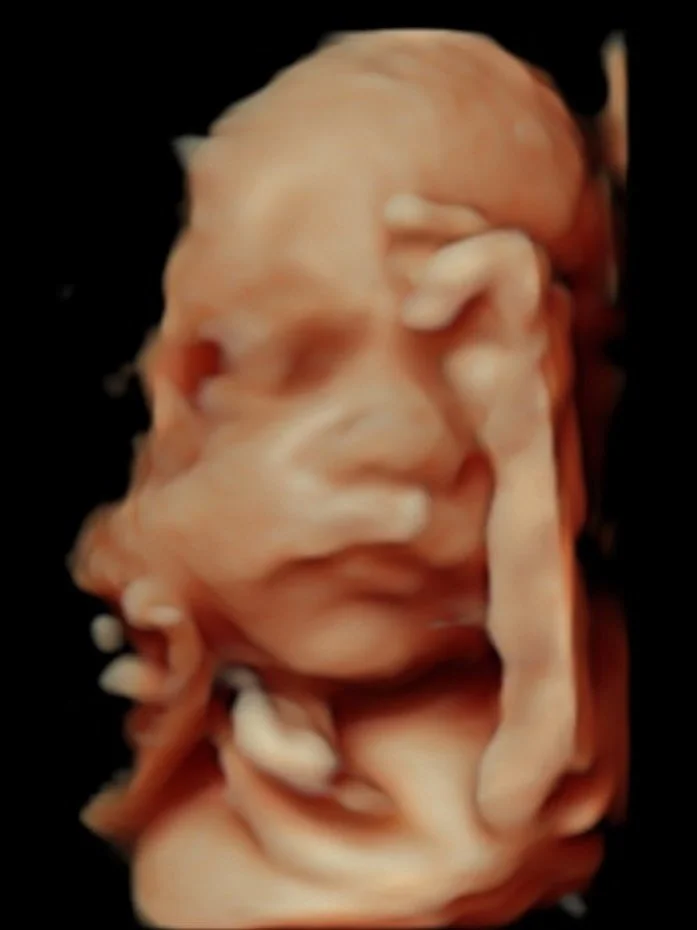

De echobeelden zijn in HD-kwaliteit en ons apparaat voldoet aan de landelijk gestelde eisen.

Wij zorgen voor beeldmateriaal van hoge kwaliteit door ons nieuwste echoapparaat welke aan de kwaliteitseisen voldoet.

Bij elke echo printen wij gratis zwart-wit foto's. Ook kunnen wij de bestanden digitaal naar je opsturen. Daarnaast is het ook mogelijk om foto's en videofragmenten mee te krijgen op een USB stick. Voor actuele prijzen van de USB sticks, klik hier. Let op: bij de 3D/4D echo's zit een USB stick inbegrepen in de prijs!